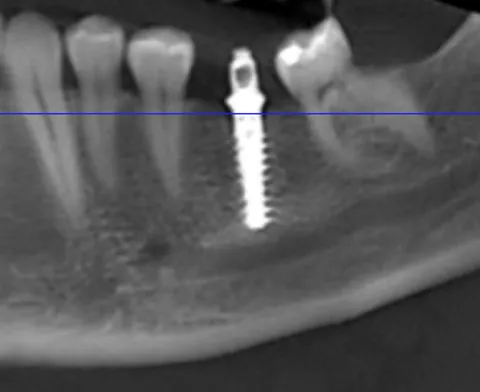

Anschließend erfolgte die Insertion des Implantates (Straumann TLX, 4.5x12 mm) mit dem Motor Implantmed (W&H) mit einer vordefinierten Eindrehkraft von 50 Ncm (Abb. 8). Die letzten 3 Gewindegänge wurden mit der Handratsche eingedreht, um die notwendige Primärstabilität mit hoher händischer Taktilität zu prüfen (Abb. 9). Die vertikale Implantatposition wurde so gewählt, dass der aufgeraute Titananteil epikrestal abschließt (Abb. 10, 11). Der maschinierte Anteil des Tissue Level Implantates ergibt somit einen Abschluss auf Gingivaniveau, wodurch eine Verschiebung der Anschlussstelle für die Prothetik weg vom ossären Niveau erfolgt und die biologische Breite sicher eingehalten werden kann. Die Primärstabilität des Implantates lag bei 50 Ncm. Eine Einheilkappe wurde aufgebracht (Bild 18) und der Wundverschluss mit nicht resorbierbarer Naht der Stärke 5-0 durchgeführt. Für einen exakten und stabilen Wundverschluss wurde der vestibuläre Weichgewebelappen kragenförmig moduliert und in Double-Sling-Technik adaptiert (Abb. 12). Das postoperative Röntgenbild zeigt die korrekte Position des Implantates mit ausreichend apikalem Abstand zum Verlauf des Nervus alveolaris inferior (Abb. 13).

Unmittelbar im Anschluss an die OP erfolgte das Aufbringen eines Scan-Bodys (Straumann, CARES) mit digitaler Abformung der Implantatposition (Abb 14). Die Daten wurden unmittelbar über eine Cloud-Lösung auf den Arbeitsplatz des Zahntechnikers übertragen. Die Anfertigung der provisorischen Krone erfolgte durch Fräsen aus einem Kunststoffblock nach rein digitaler Planung (Abb. 15, 16; Labor Jörg Bies) in einem Zeitrahmen von zwei Stunden. Die provisorische Krone wurde direkt auf dem Implantat verschraubt (Abb. 17). Insbesondere wurde beim Einsetzen darauf geachtet, die periimplantäre Schleimhaut durch das Emergenzprofil der provisorischen Krone zu stützen. Die Okklusion wurde geprüft und die statische und dynamische Okklusion so weit reduziert, dass eine Interferenz durch Früh- und Störkontakte sicher ausgeschlossen werden konnte. Das postoperative Panoramaröntgenbild zeigt den korrekten Sitz von Implantat und Krone. Der Fadenzug erfolgte nach zehn Tagen bei sehr gut abgeheilten Wundverhältnissen.

Sechs Monate nach Implantation erfolgte die klinische und radiologische Kontrolle des Implantates. Bei solider Osseointegration und stabilen Schleimhautverhältnissen erfolgte daraufhin die Freigabe für die finale prothetische Versorgung des Implantates (Abb. 18).

Abb. 18: Röntgenkontrolle sechs Monate nach Insertion mit hervorragender Osseointegration unter Belastung.